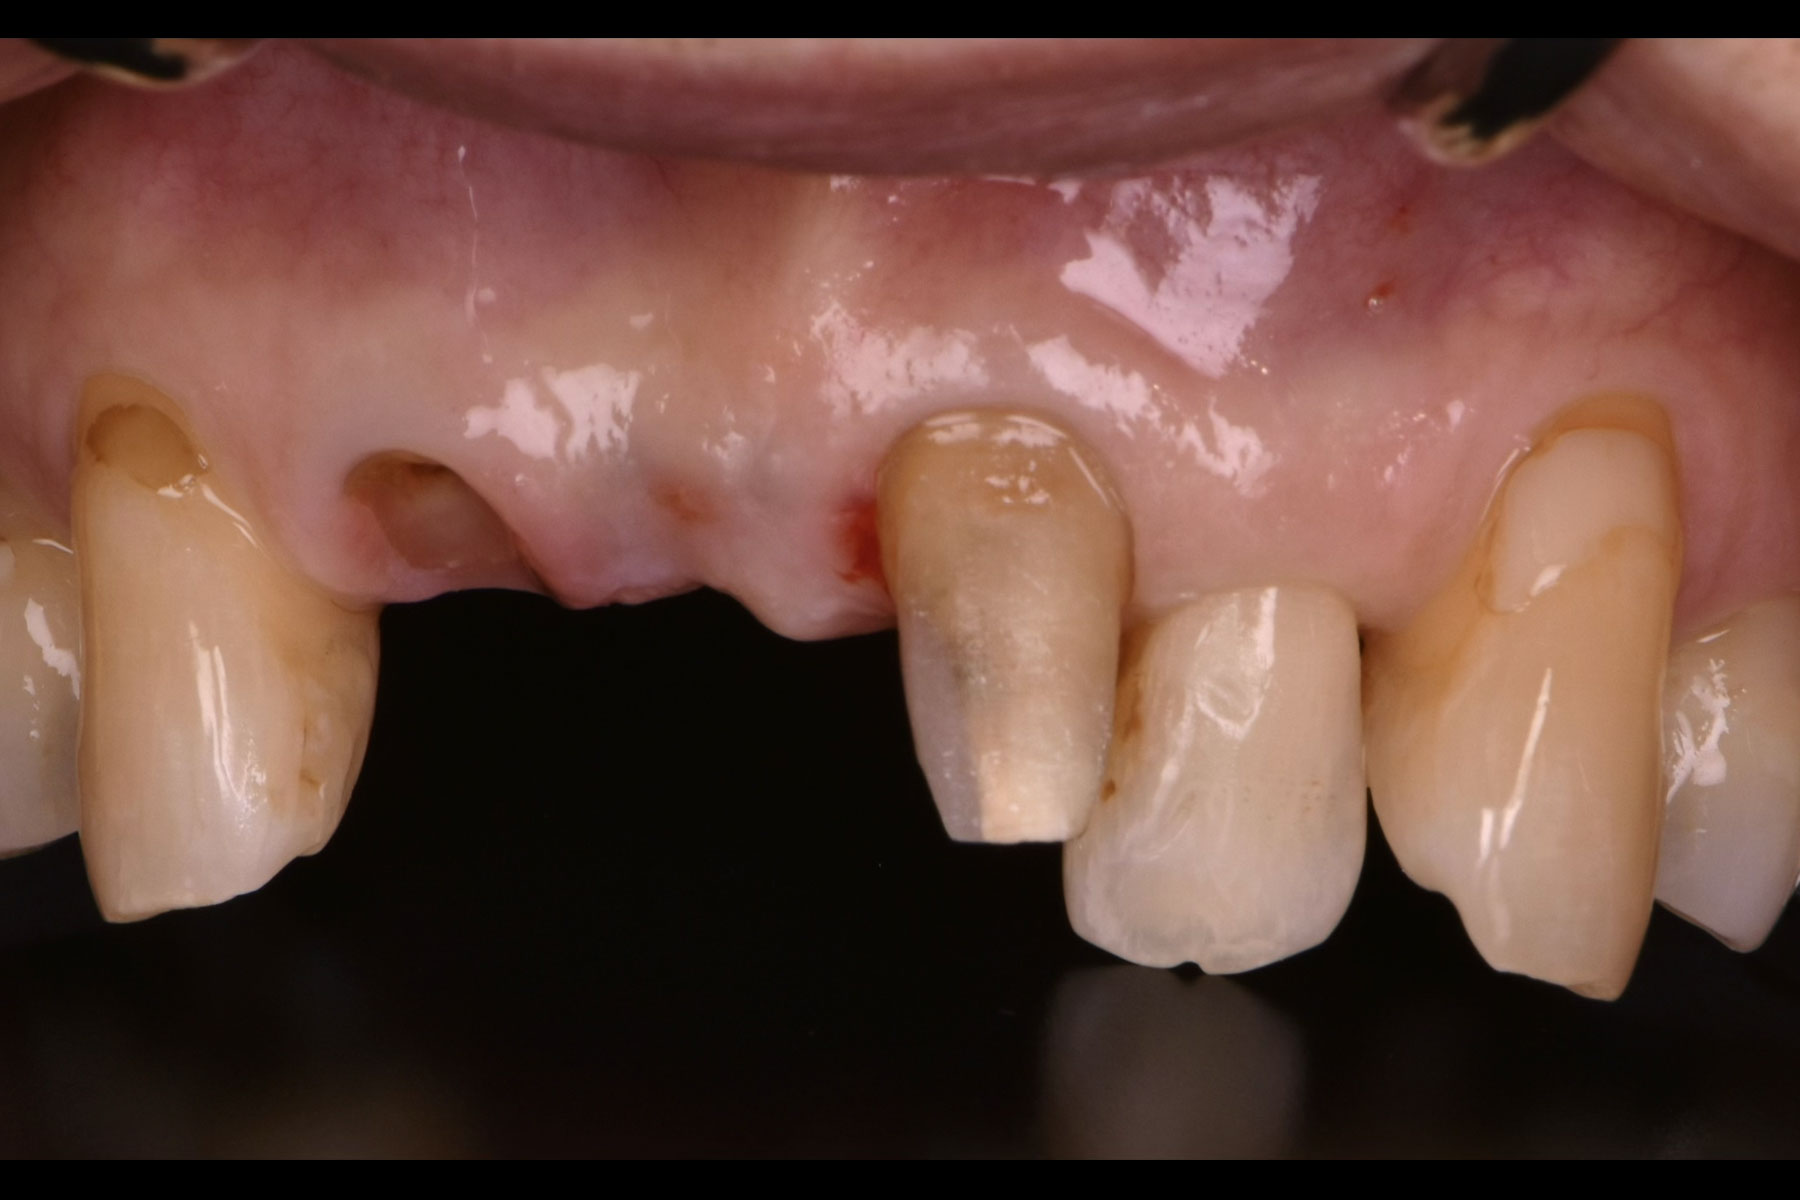

治療前

| 主訴 | 前歯が割れているため抜かなければいけないと言われた |

| 治療内容 | インプラント治療 |